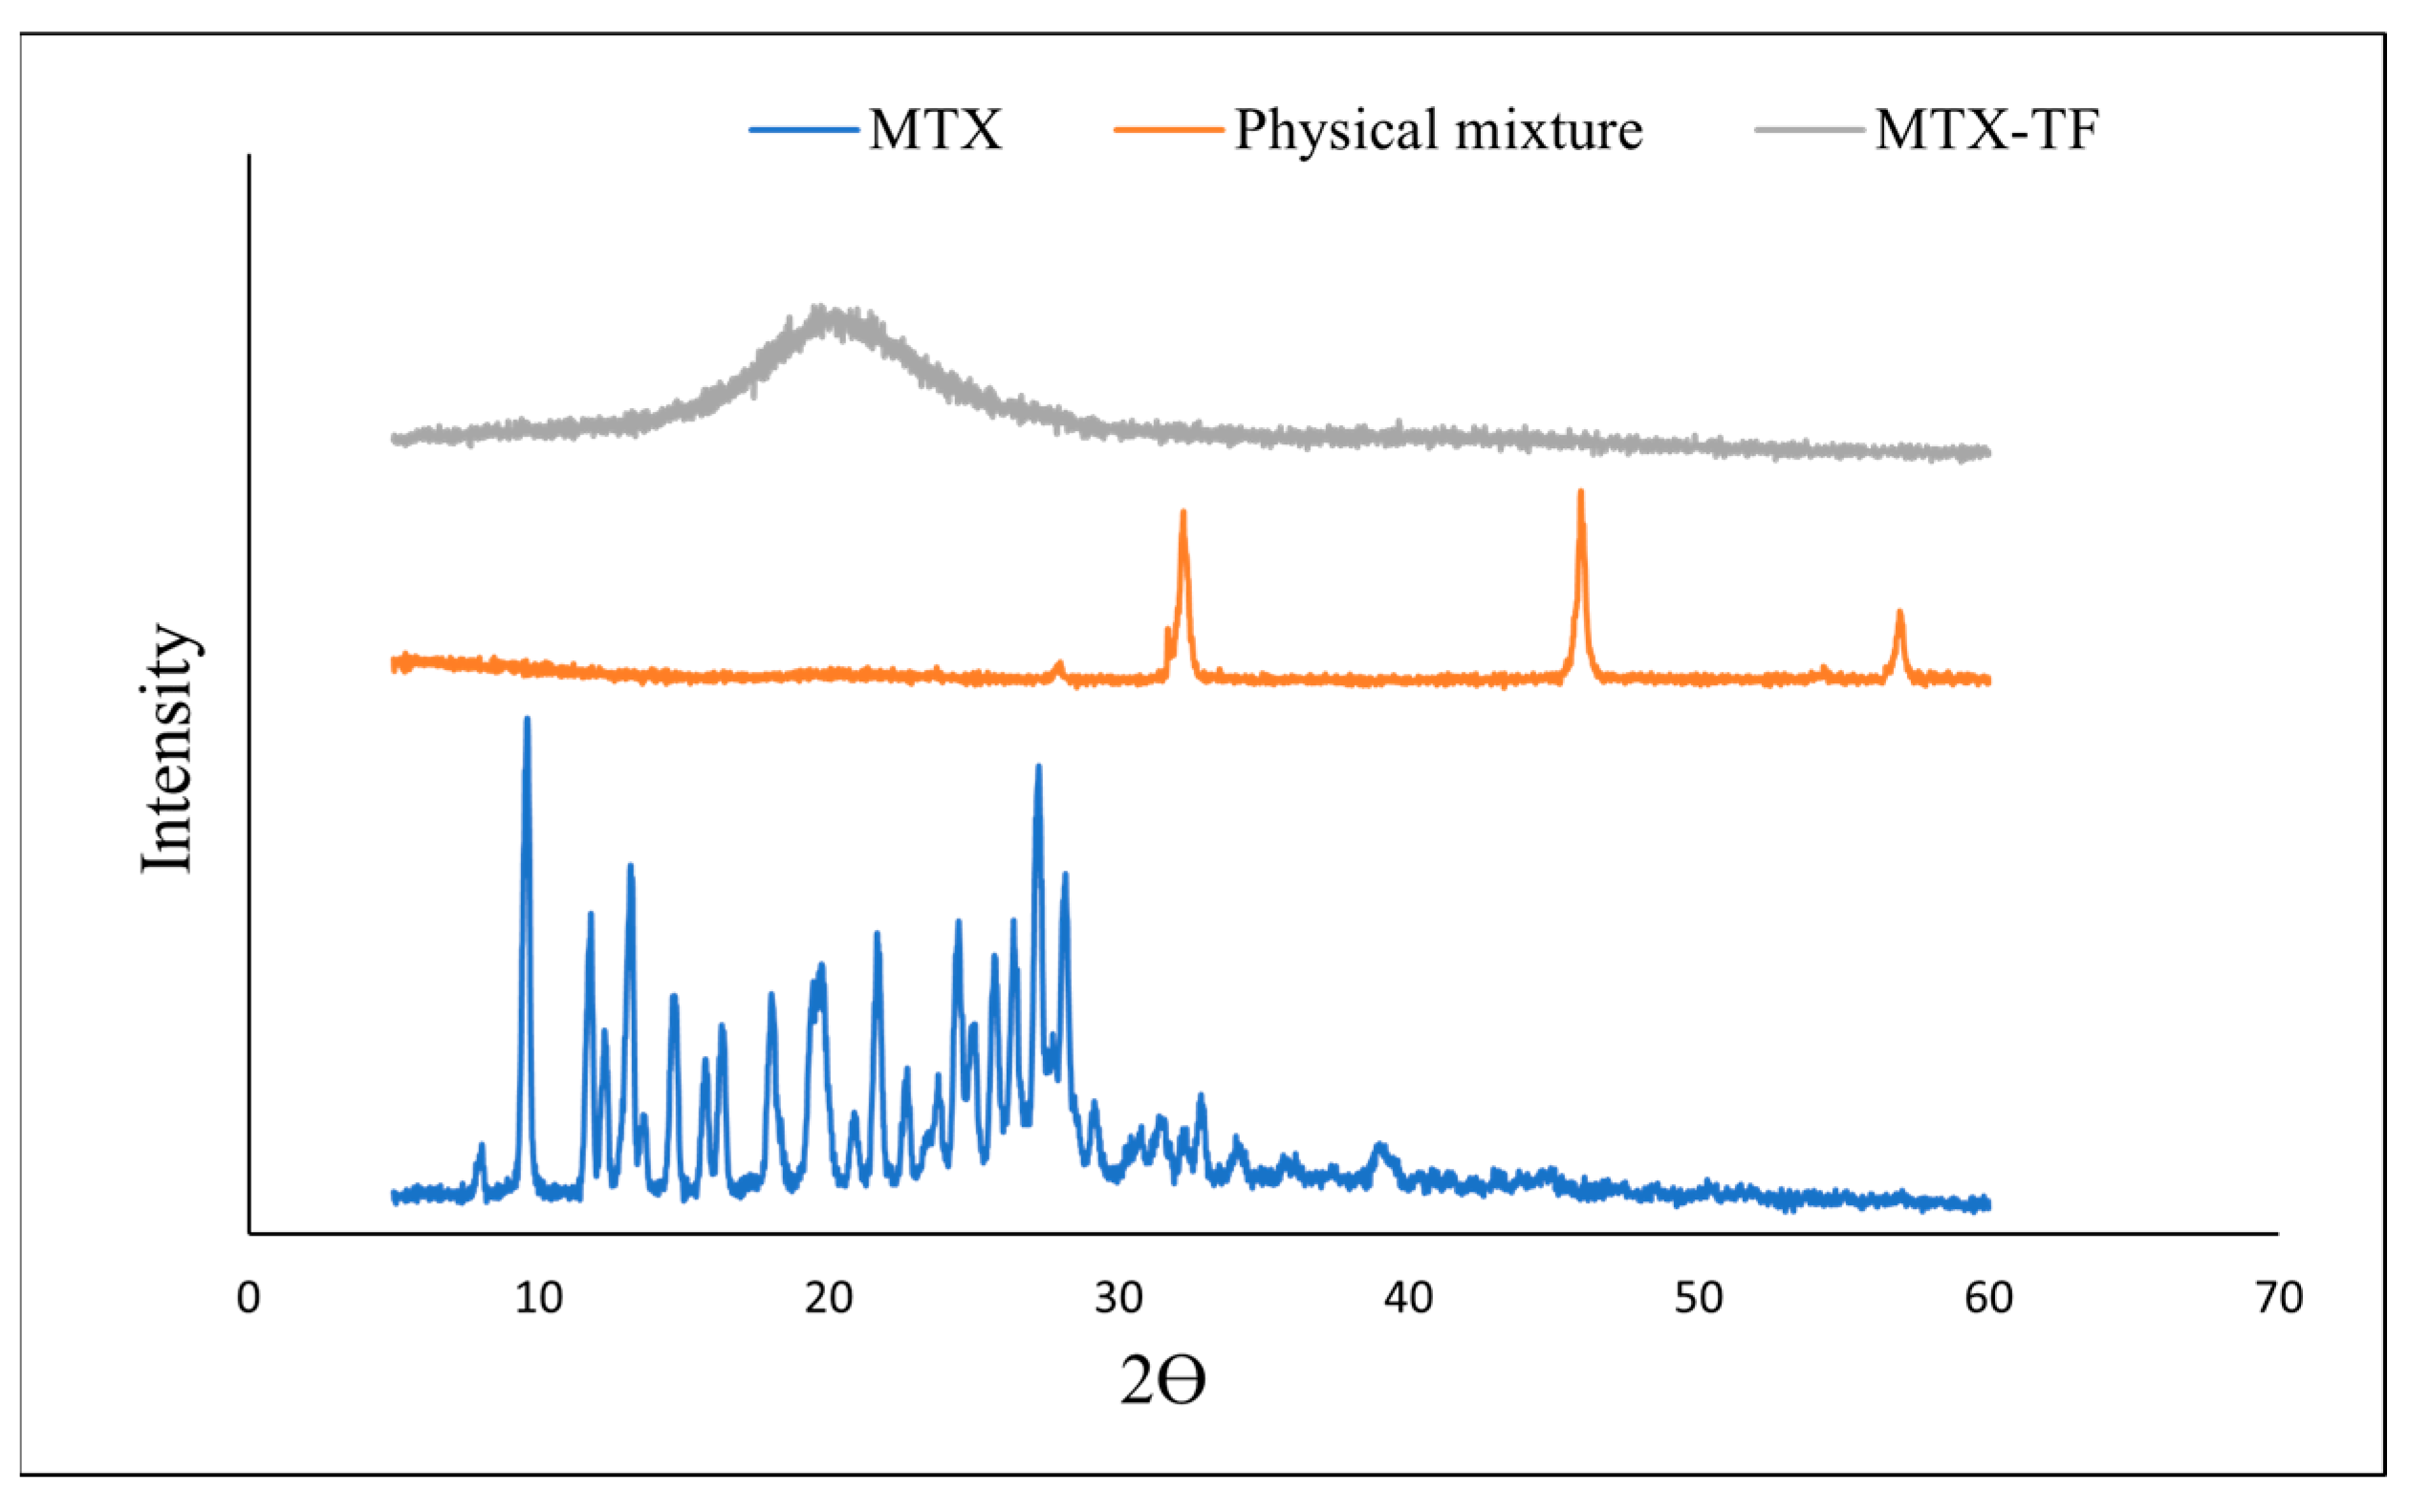

2.5.4. X-Ray Diffraction

3.2.9. X-Ray Diffraction